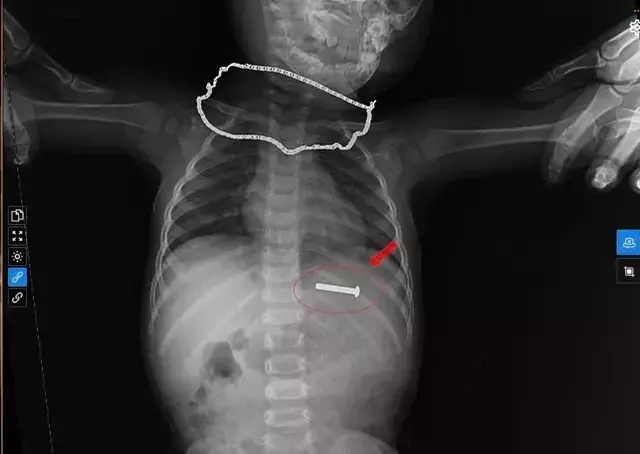

Những hình ảnh đầu tiên về chiếc đinh vít 5 cm nằm trong dạ dày qua nội soi gây chấn động cộng đồng y tế. Chiếc đinh này không chỉ là một dị vật nguy hiểm mà còn là thách thức lớn đối với kỹ thuật nội soi. Các bác sĩ tại Bệnh viện Minh An đã phải hành động nhanh chóng để ngăn chặn những biến chứng có thể xảy ra.

Khi nhận được thông tin, các bác sĩ đã tiến hành chụp X-quang và siêu âm để xác định vị trí của dị vật. Kết quả cho thấy chiếc đinh vít đã nằm trong dạ dày của bệnh nhi. Ngay lập tức, ê kíp nội soi đã chuẩn bị để thực hiện thủ thuật gắp dị vật dưới gây mê. Sau 15 phút, họ đã thành công trong việc gắp ra chiếc đinh vít xoắn dài 5 cm từ dạ dày của bệnh nhi.